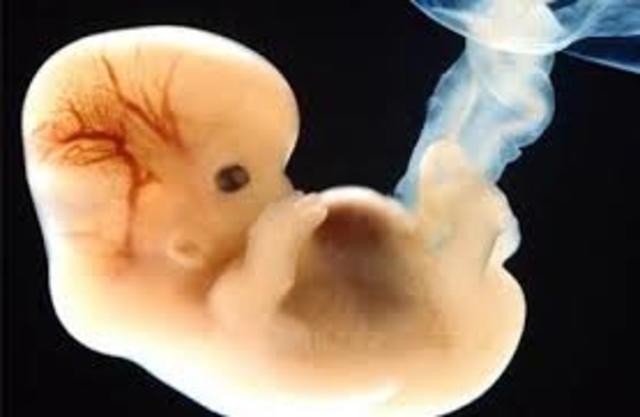

• (Embrión 6-8 semanas):

(Embrión 6-8 semanas):

El corion es una envoltura externa que recubre el embrión humano y que participa en la función de la placenta